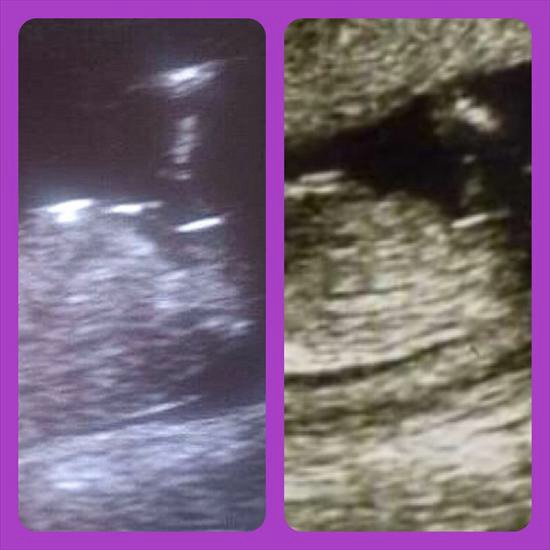

I have lightened my picture and found another confirmed girl picture to compare it to. My pic is on the left and the confirmed girl one is on the right. Do the nubs look similar? Would you say I'm have in a girl too? XAttachment 16432